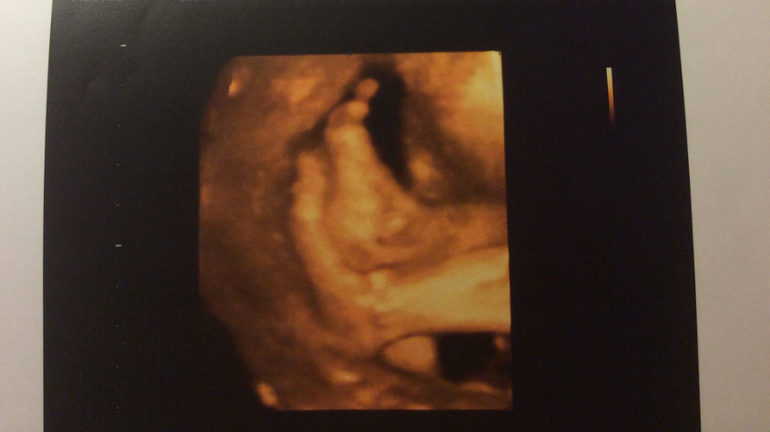

По последним 3d узи, которые я делала в Москве, все хорошо с малышкой. Только сидела пока на попе. или вообще поперек, вытянув ножки, как на шезлонге) потом фото приложу. Ножки мои по фото, все говорят. А вот носик пока кажется картошечкой) но может просто личико маленькое. Главное - что здорова вроде! надеюсь, за 2 недели перевернется.

P.S. Прикреплю и дочины фото на память. Буду вспоминать, как она там ножку на ногу лежала с вытянутыми ножками, как за пуповину держалась ручкой, как -будто в трамвае за перекладину)